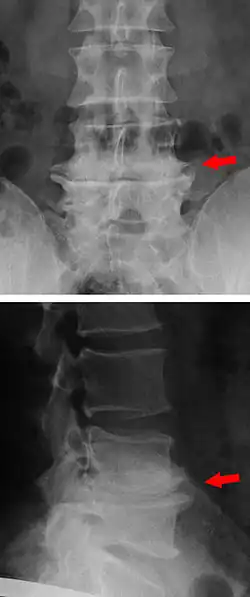

Die Formveränderung der Wirbelkörper im Sinne der Spondylophyten (Spondylose) und die Minderung des Zwischenwirbelraums durch Höhenverlust der Bandscheiben sind im konventionellen Röntgenbild gut sichtbar. Auch der Verschleiß der Wirbelbogengelenke (Spondylarthrose) zeigt sich hier deutlich.

Eine genauere Einschätzung erlaubt die Durchführung einer CT-Untersuchung oder eines MRT. Hier können frühe Stadien der Osteochondrose, nämlich eine vermehrte Durchblutung des Knochenmarks nahe der Deckplatten der Wirbelkörper, von den später eintretenden Umwandlung dieses Gewebes, die „fettige Degeneration“, unterschieden werden. In der Radiologie werden anhand der Modic-Klassifikation verschiedene drei Stadien unterteilt.